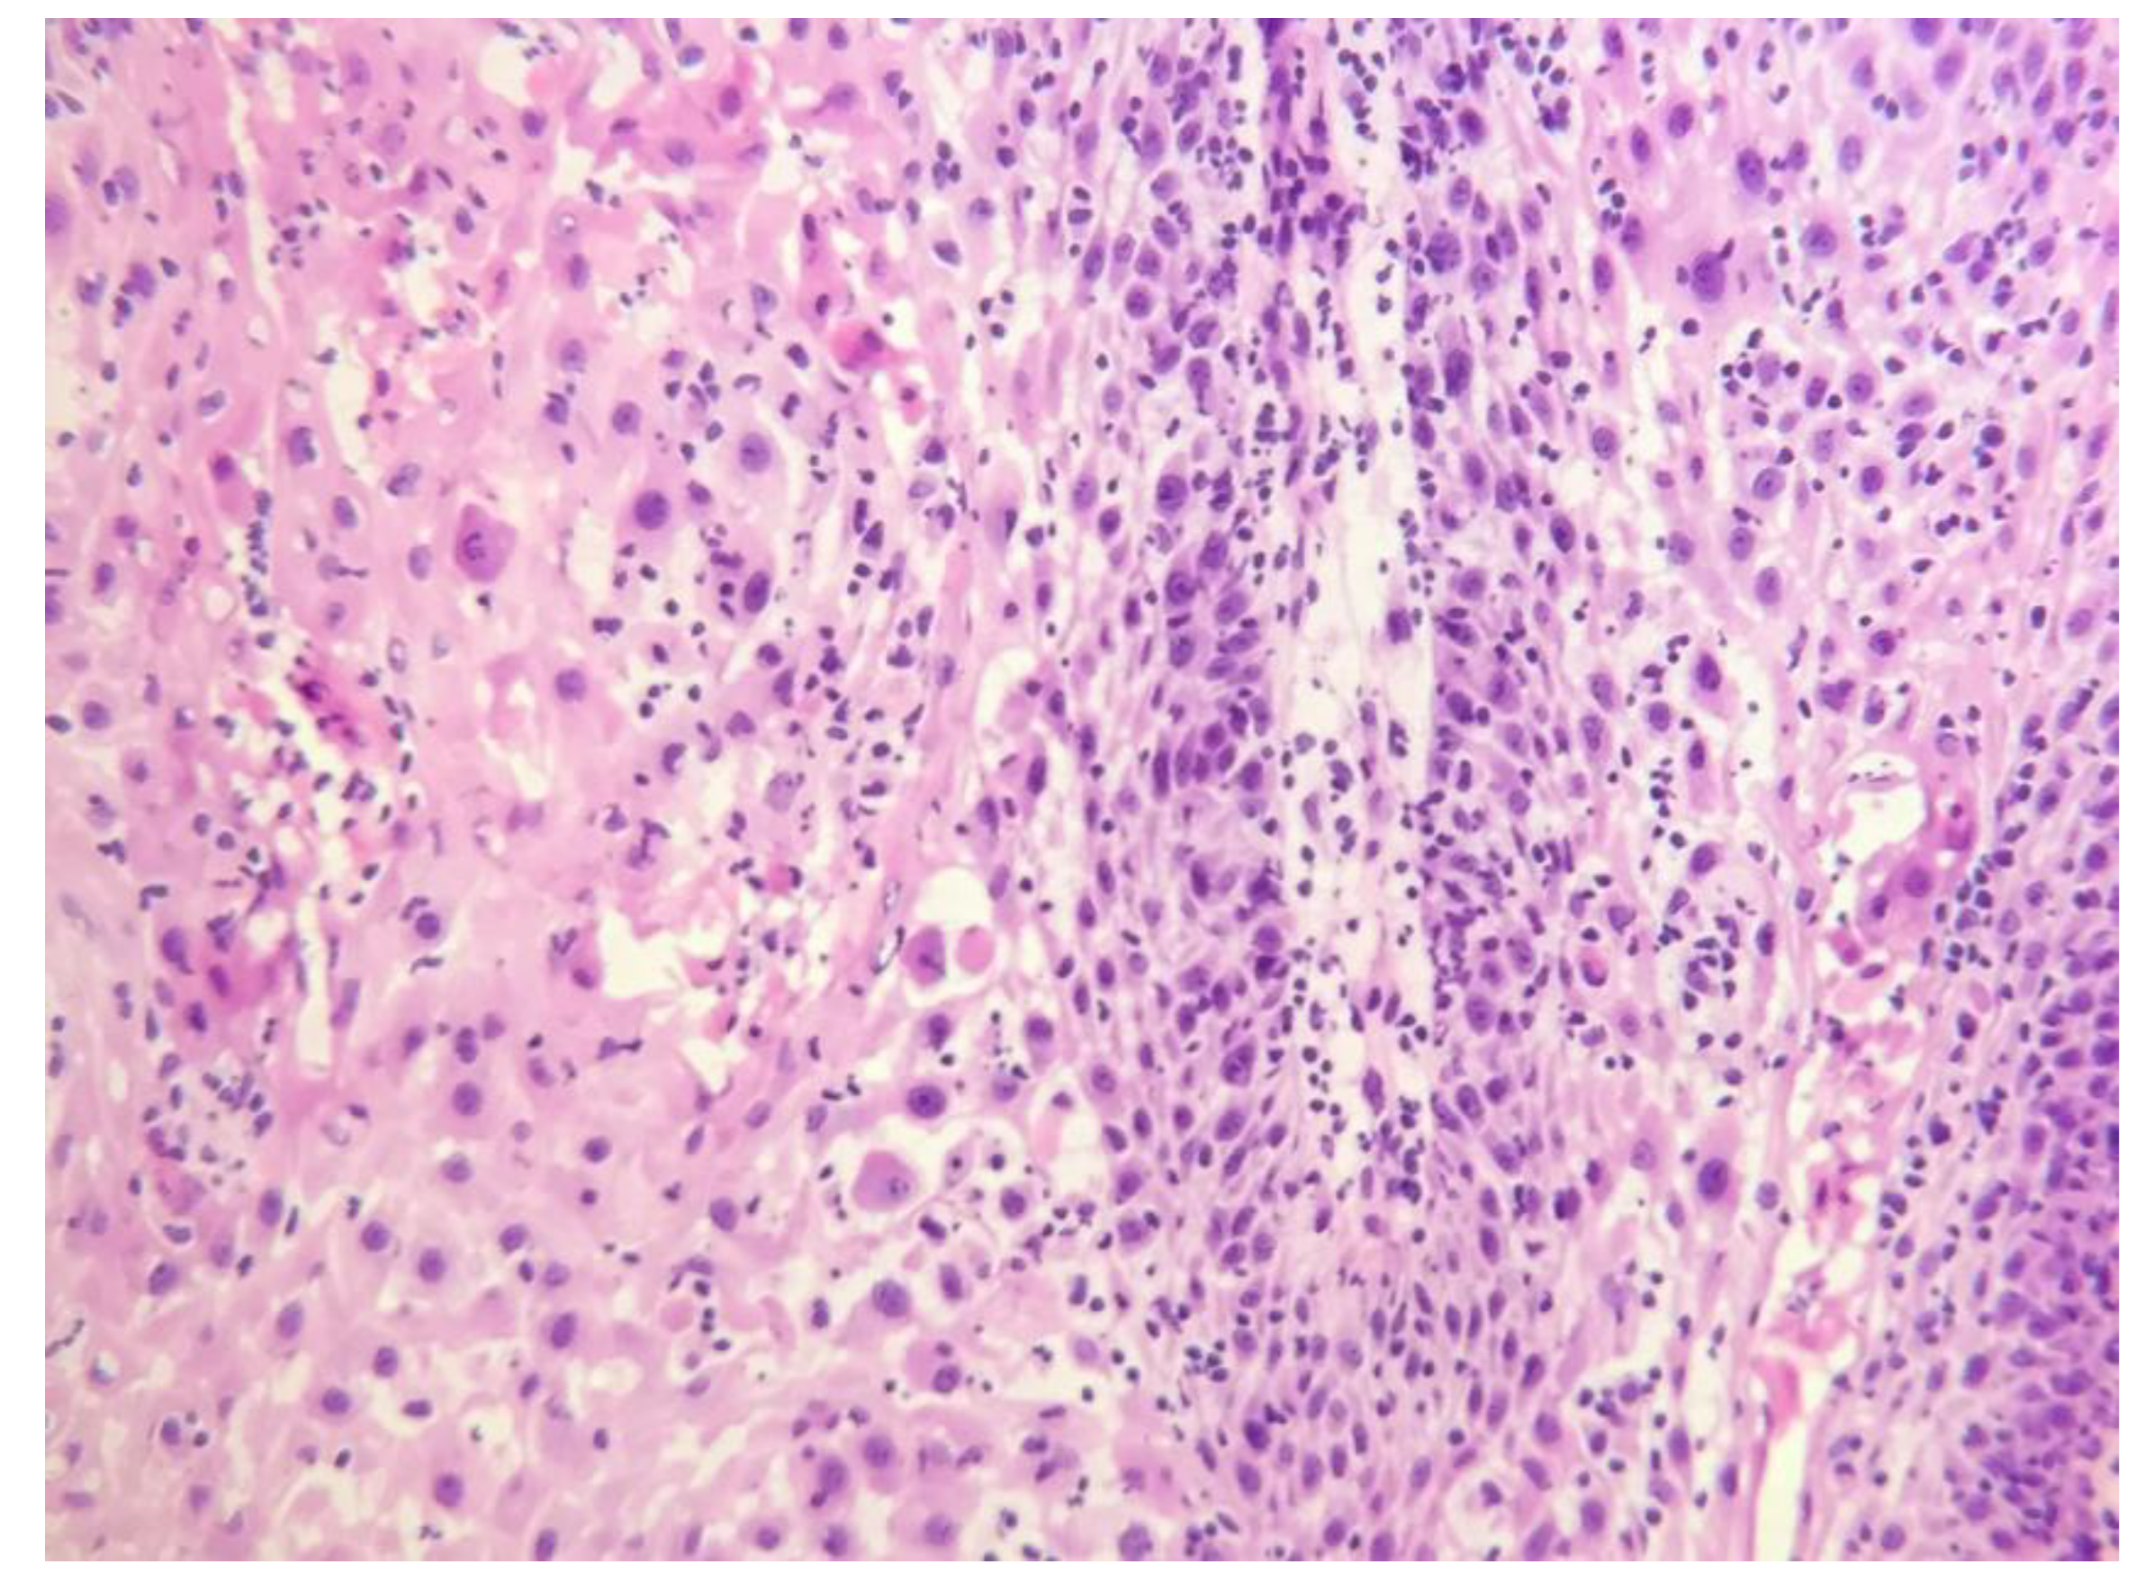

Histopathological examination of the specimen from the permanent biopsy revealed a proliferation of well-differentiated epithelium with minimal atypia at the epithelial connective tissue interface (Figure 4). Cleft-like spaces lined by a layer of parakeratin extended from the surface deep into the lesion. These findings were consistent with verrucous carcinoma.

Microscopically this tumor is characterized by predominant exophytic overgrowth of well-differentiated keratinizing epithelium having minimal atypia associated with in-tense chronic inflammatory infiltrate. The pathological diagnosis of verrucous carcinoma is not so difficult. However, in some cases, small or superficial biopsy specimens may only exhibit hyperkeratosis, acanthosis and papillomatosis. Therefore, in some cases, verrucous carcinoma, appearing benign with "pushing" borders and an intact basement mem-brane, can be mistaken for a benign lesion histologically. Deeper and adequate biopsy specimens, along with a sufficient volume, must be obtained whenever verrucous carcinoma is suspected for a definitive diagnosis. In fact, multiple biopsies are sometimes recommended for diagnosing verrucous carcinoma [16].

Figure 4. Surgical Pathology Findings Post-Operation. The histopathological examination of the specimen revealed a proliferation of well-differentiated epithelium with minimal atypia at the epithelial-connective tissue interface which indicated squamous cell carcinoma. (H&E, x100).